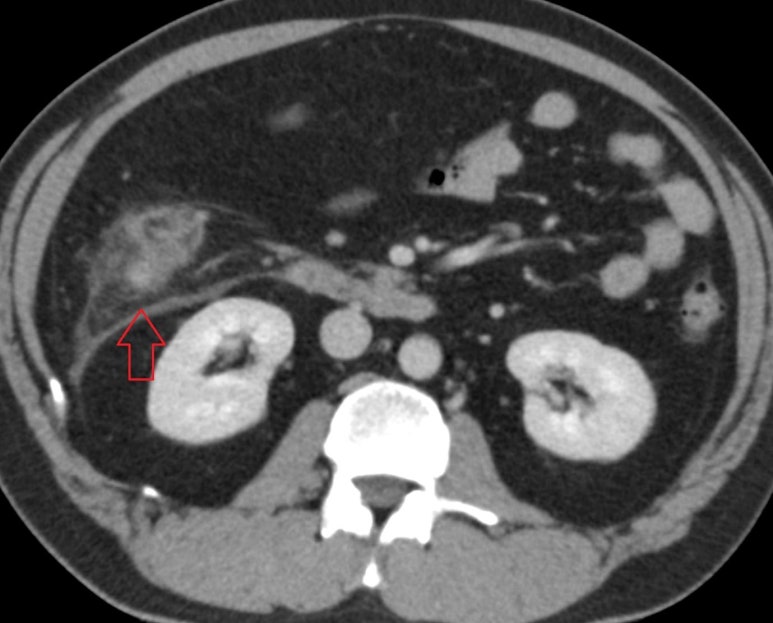

발열 복통으로 오셔서 게실염이 발견된 사례